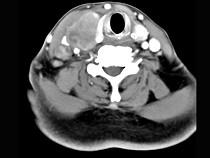

问题 女性,54岁,右侧颈部肿大近1年,近来病人有声嘶、吞咽困难,CT扫描如图,请选择正确的描述和答案()

选项 A.右侧甲状腺肿大,密度减低 B.增强扫描示甲状腺呈不规则强化团块影,其内有低密度区,病灶境界不清 C.右侧颈内静脉增粗,其内可见不规则充盈缺损区 D.考虑甲状腺癌 E.右侧颈内静脉瘤栓形成

答案 ABCDE